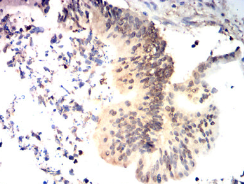

KMT2A Mouse Monoclonal antibody[7E1D]

This gene encodes a transcriptional coactivator that plays an essential role in regulating gene expression during early development and hematopoiesis. The encoded protein contains multiple conserved functional domains. One of these domains, the SET domain, is responsible for its histone H3 lysine 4 (H3K4) methyltransferase activity which mediates chromatin modifications associated with epigenetic transcriptional activation. This protein is processed by the enzyme Taspase 1 into two fragments, MLL-C and MLL-N. These fragments reassociate and further assemble into different multiprotein complexes that regulate the transcription of specific target genes, including many of the HOX genes. Multiple chromosomal translocations involving this gene are the cause of certain acute lymphoid leukemias and acute myeloid leukemias. Alternate splicing results in multiple transcript variants.

Immunogen :   Purified recombinant fragment of human KMT2A (AA:150-400) expressed in E. Coli.

IHC    1/200 - 1/1000